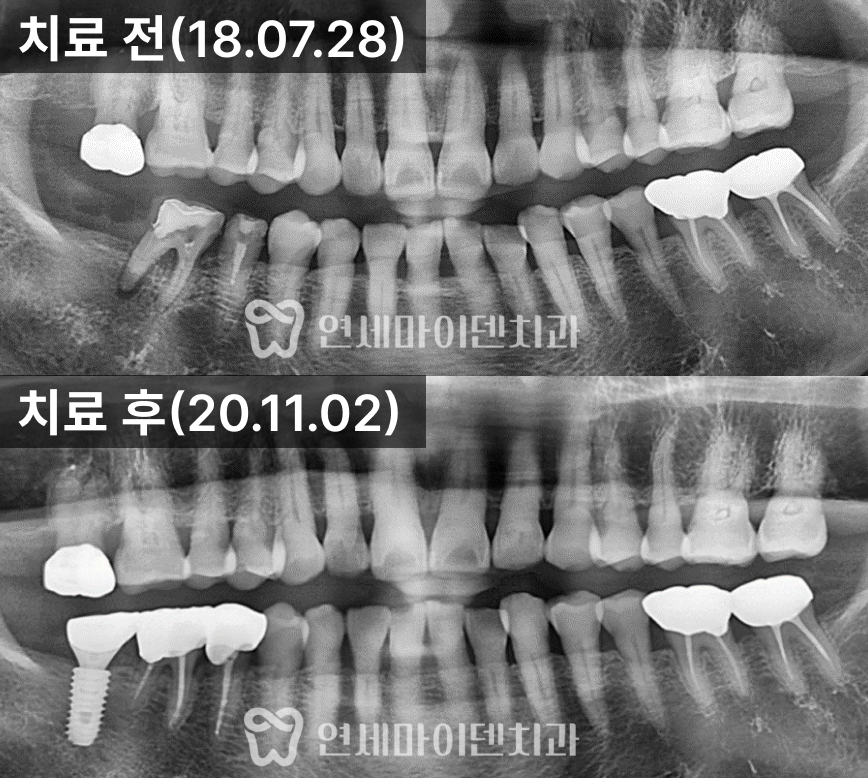

자연스러운 형태로 제작해서 올려주었습니다.치료 경과 및 예후

3년간의 추적 관찰 결과, #26번 임플란트는

주변 잇몸과 뼈의 안정성이 매우 양호한 상태로 유지되고 있습니다.#25번 재신경치료 부위 역시 염증이 완전히 소실되어,

통증 없이 자연치아처럼 사용 중이십니다.치료 전에는 불편감이 지속되던 부위가 현재는 완전히 회복되어

식사 시에도 전혀 불편함이 없다고 말씀하셨습니다.